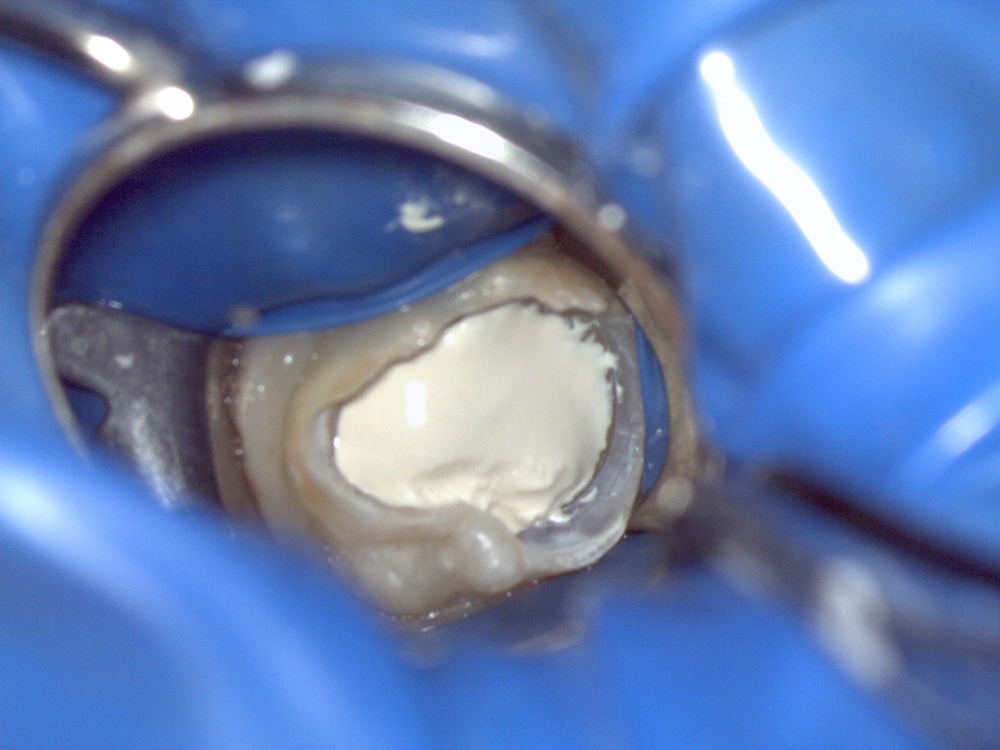

治療中,牙醫師會視狀況局部麻醉,並以高倍放大設備完整清除患部,並在消毒後以特殊生醫材料將牙髓覆蓋後密封與復形。整個過程中將會拍攝術前及術後X光片。由於治療複雜化費時間較長,治療次數依不同牙齒難易而不同,需一至兩次約診,每次治療時間約 0.5-1 小時。

清除感染牙髓組織後,放入生醫材料

緊密填補,避免細菌從隙縫再度入侵